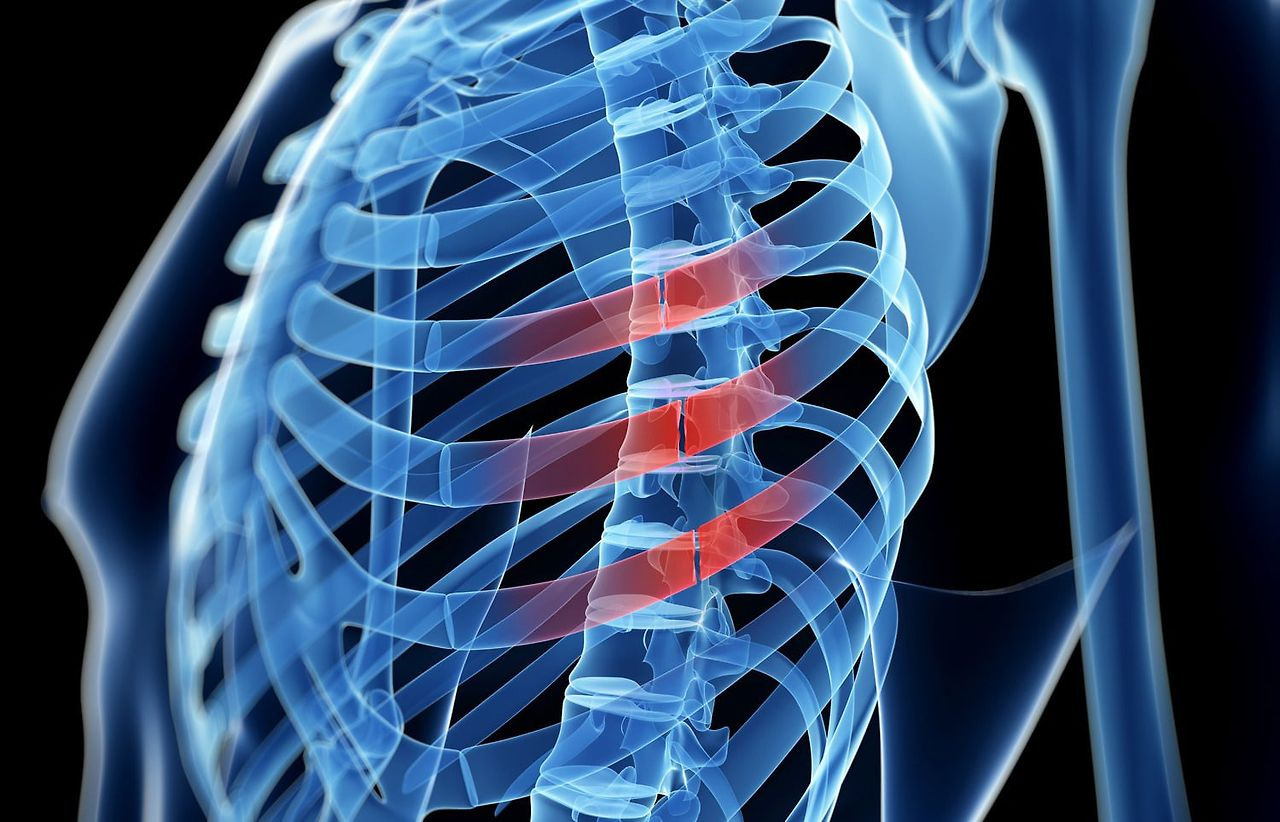

갈비뼈 금간 증상

갈비뼈가 금이 가거나 부러지는 것은 흔히 발생할 수 있는 부상 중 하나입니다. 특히, 교통사고, 낙상, 스포츠 부상과 같은 충격으로 인해 갈비뼈에 손상이 가는 경우가 많습니다. 갈비뼈가 금이 가면 특별한 증상들이 나타나며, 이러한 증상은 회복 기간과 치료 방법에 영향을 미칩니다. 다음은 갈비뼈에 금이 갔을 때 나타날 수 있는 주요 갈비뼈 금간 증상들입니다.